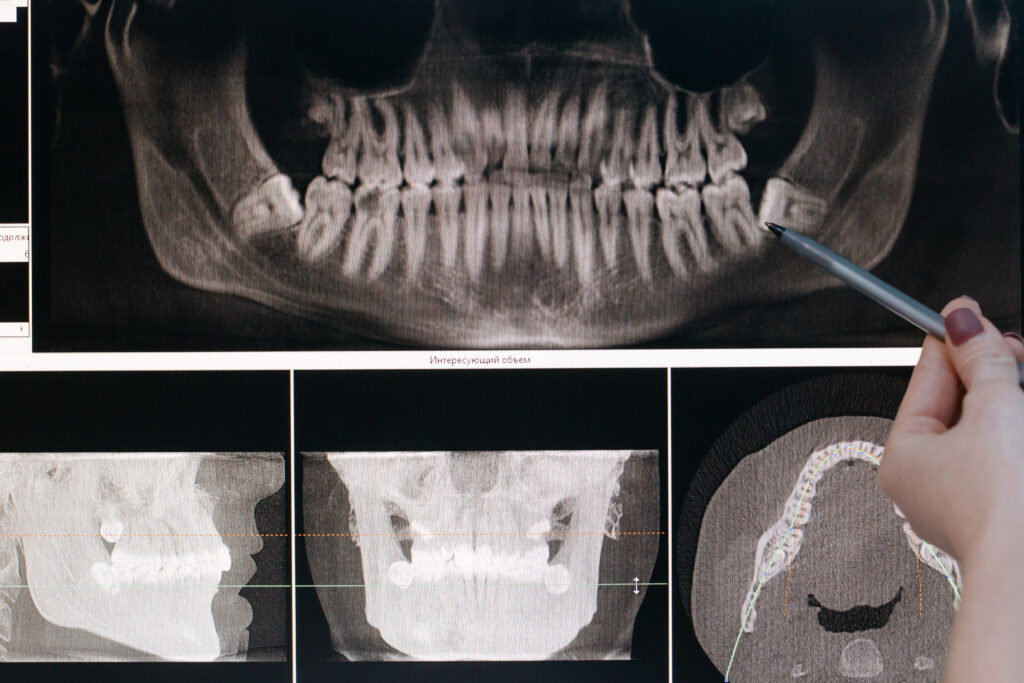

Digital X Ray Means Digital radiography is filmless, and allows immediate acquisition, deletion, editing and transfer of films to a computer system which generates the image almost at once. For patients who need frequent imaging, this considerable reduction can contribute significantly to their safety. Digital radiography is filmless, and allows immediate acquisition, deletion, editing and transfer of films to a computer system which generates the image almost at once. This innovation has transformed the field of.